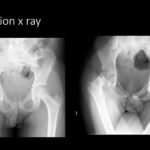

Slipped Capital Femoral Epiphysis

Courtesy: Amr Abdelgawad, Maimonaides Medical Centre, Brooklyn, New York, USA